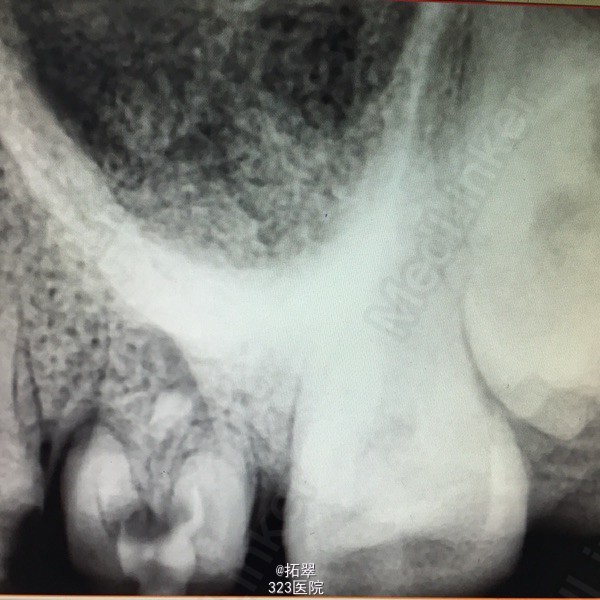

左上后牙咬合不适数月,偶有夜间痛。

左上6金属冠,叩(+)冷(-),松(-) 左上5远中颌面缺损,冷(+),叩(-),松(-) X线检查:左上6髓腔内充填物,根尖少于阴影,根管内未见充填物。 左上5龋深及髓。

诊断:左上6尖周炎 左上5慢性牙髓炎 建议:左上6根管再治疗后+桩+冠修复 左上5RCT+桩+冠 处理:左上6拆冠,清理根管,MB、DB长16mm,扩至F1,P长17mm,扩至F1,双氧水反复冲洗,木馏油棉开放 左上5开髓,置乳失,丁香油棉安抚,ZOE暂封。